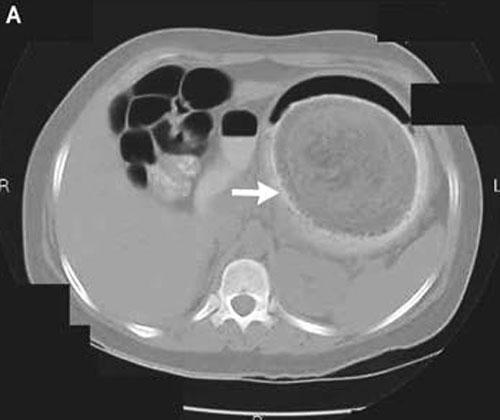

В ноябре 2007 года американский медицинский журнал опубликовал статью, в которой рассказывается история 18-летней девушки поедавшей свои волосы…Пациентка поступила в одну из больниц Новой Англии с жалобами на острую боль в желудке… Примерно на протяжении последних пяти месяцев девушка неуклонно теряла в весе и к моменту прибытия в больницу потеряла около 18 килограмм.

С помощью эндоскопа доктора исследовали содержимое и состояние желудка пациентки, и, к своему удивлению, обнаружили там огромный волосяной ком, которой никак невозможно было удалить через маленькие разрезы… Пришлось производить традиционную хирургическую операцию.

Из желудка девушки была извлечена масса волос весом … 4,5 килограмма… А пациентке после хирургического вмешательства посоветовали обратиться к психиатру…